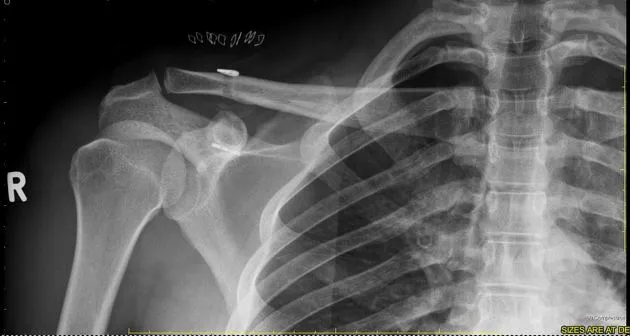

Röntgenfoto: er worden röntgenfoto’s gemaakt van de schouder. Hierop is te zien of het sleutelbeen uit de kom is en hoeveel speling er is. Bij twijfel kan een foto met gewichten in de handen (stress opname) de mate van AC-luxatie beter zichtbaar maken.

Een AC-luxatie is een ontwrichting van het gewricht tussen sleutelbeen (clavicula) en schouderdak (acromion). Dit letsel ontstaat typisch door een val op de schouder en veroorzaakt pijn en soms een zichtbare bult op de schouder. De diagnose is meestal klinisch duidelijk en kan bevestigd worden met een röntgenfoto. In de meeste gevallen hoeft een AC-luxatie niet geopereerd te worden en volstaat een behandeling met rust (mitella) en oefentherapie. Bij ernstige gevallen herstelt de schouder na een operatie ook goed. Met de juiste begeleiding en revalidatie krijgen de meeste patiënten hun schouderfunctie weer terug.